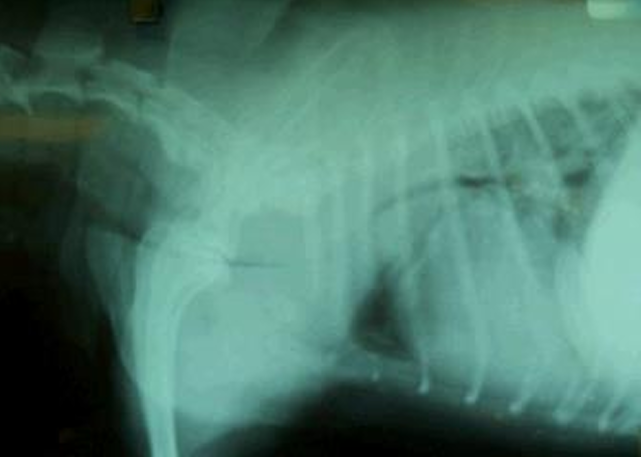

| ํก๊ธฐ ์ดฌ์ | ํธ๊ธฐ ์ดฌ์ |

|---|---|

![]() | ![]() |

| Trachea์ bifurcation๊น์ง์ ๊ธฐ๊ด ์ง๊ฒฝ์ด ๊ด์ฐฎ์ ๋ณด์. | Bifurcation ๋์๋ฝ์ด collapsed, bronchus ์ข์์ ธ ์ ๋ณด์. โ BC๋ก ์ง๋จ |

BC๋ฅผ ์ง๋จํ๊ธฐ ์ํด fluoroscopy๋ฅผ ๋ณด๋ฉด ๋์์ด ๋ง์ด ๋จ.

Trachea์ esophagus๊ฐ ๊ฒน์น ์์์ ๊ธฐ๊ด ์ง๊ฒฝ์ด ์ค์ด๋ ๊ฒ์ผ๋ก ๋ณด๊ณ TC๋ก ์ค์งํ๋ฉด ์ ๋จ.